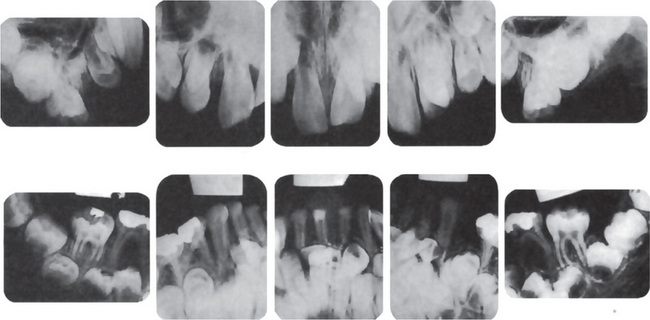

The childhood form is characterized by rachitic deformities. Upon radiologic examination of the metaphysis, evidence of radiolucent projections from the epiphyseal plate into the metaphysis is present. This is not found in other types of rickets. Radiographic findings are normal for patients with odontohypophosphatasia. Dental radiographs generally reveal hypocalcification of teeth and the presence of large pulp chambers, as well as alveolar bone loss; however these findings have not been consistently reported.

The jaws are involved in the same manner as the other bones in the body, and the oral manifestations have been reviewed by Kaslick and Brustein. However, a clear distinction has usually not been made as to the type of the disease present, benign or malignant. The medullary spaces of the jaws are remarkably reduced in both dominant and recessive osteopetrosis so that there is a marked predilection for the development of osteomyelitis should infection gain entrance to the bone. This is a complication of dental extraction which has been reported frequently and discussed by Dyson. Similar findings were noted by Bjorvatn and his associates in four children with the malignant form of the disease. They stressed the necessity of administering large doses of antibiotics to control the recurring infection, which even then did not prevent the progressive osseous destruction. Fracture of the jaw during tooth extraction, even when the extraction is performed without undue force, may also occur because of the fragility of the bone. It has been reported that the teeth are of defective quality, enamel hypoplasia, microscopic dentinal defects and arrested root development all having been described. However, this may not be true in the benign dominant form of the disease. It is also reported that the teeth are especially prone to dental caries. Since dental findings have been recorded in so few cases, this observation is difficult to evaluate. An additional rather constant finding is retardation of tooth eruption due to the sclerosis of bone.

Radiographic features are usually diagnostic. Because the disease is a heterogeneous group of disorders, the findings vary depending on the subtype. Patients usually have generalized osteosclerosis. Bones may be uniformly sclerotic, but alternating sclerotic and lucent bands may be noted near the ends of long bones (Fig. 17-6). The bones might appear club like or show an appearance of a bone within bone (endobone). The entire skull is thickened and dense, especially at the base. Sinuses are small and underpneumatized. Vertebrae are extremely radiodense. They may show alternating bands, known as the ‘rugger-jersey’ sign. Radiographs may show evidence of fractures or osteomyelitis. When the jaws are affected, the density of the bone may be such that the roots of the teeth are nearly invisible on the dental radiograph.